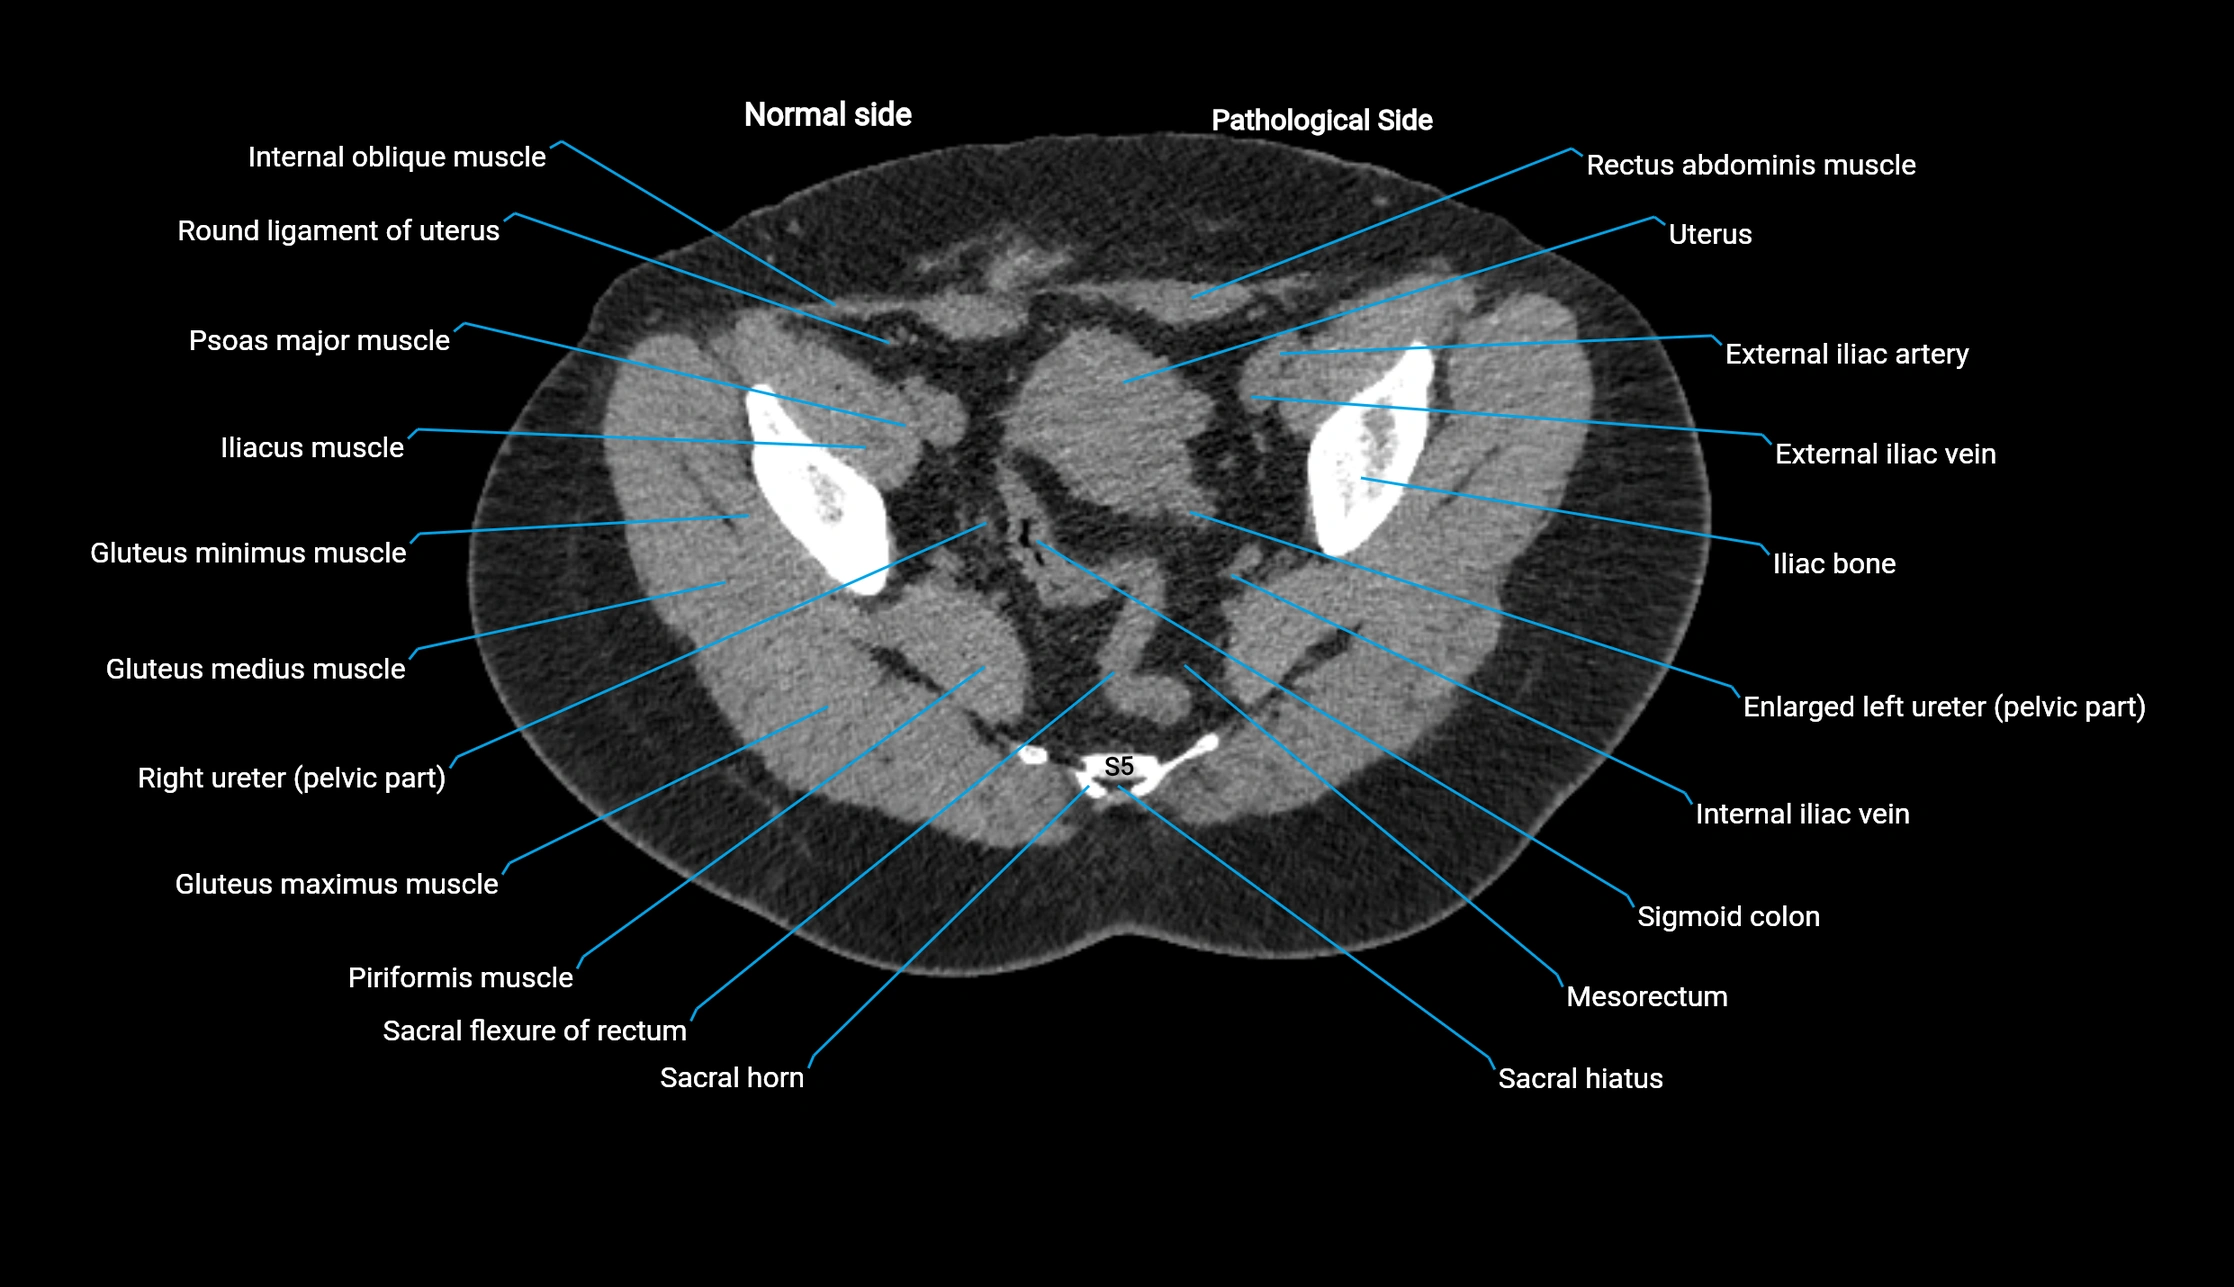

CT Appearance

Non-contrast CT:

• Demonstrates cortical bone of acetabular rim in excellent detail

• Detects fractures, dysplasia, retroversion, or bony overcoverage (pincer impingement)

• 3D reconstructions used in preoperative hip surgery planning

CT Post-Contrast (CT Arthrography):

• Joint contrast outlines the acetabular labrum, cartilage, and margin

• Demonstrates labral tears, cartilage defects, and subtle bony abnormalities

• Alternative to MR arthrography in patients with MRI contraindications